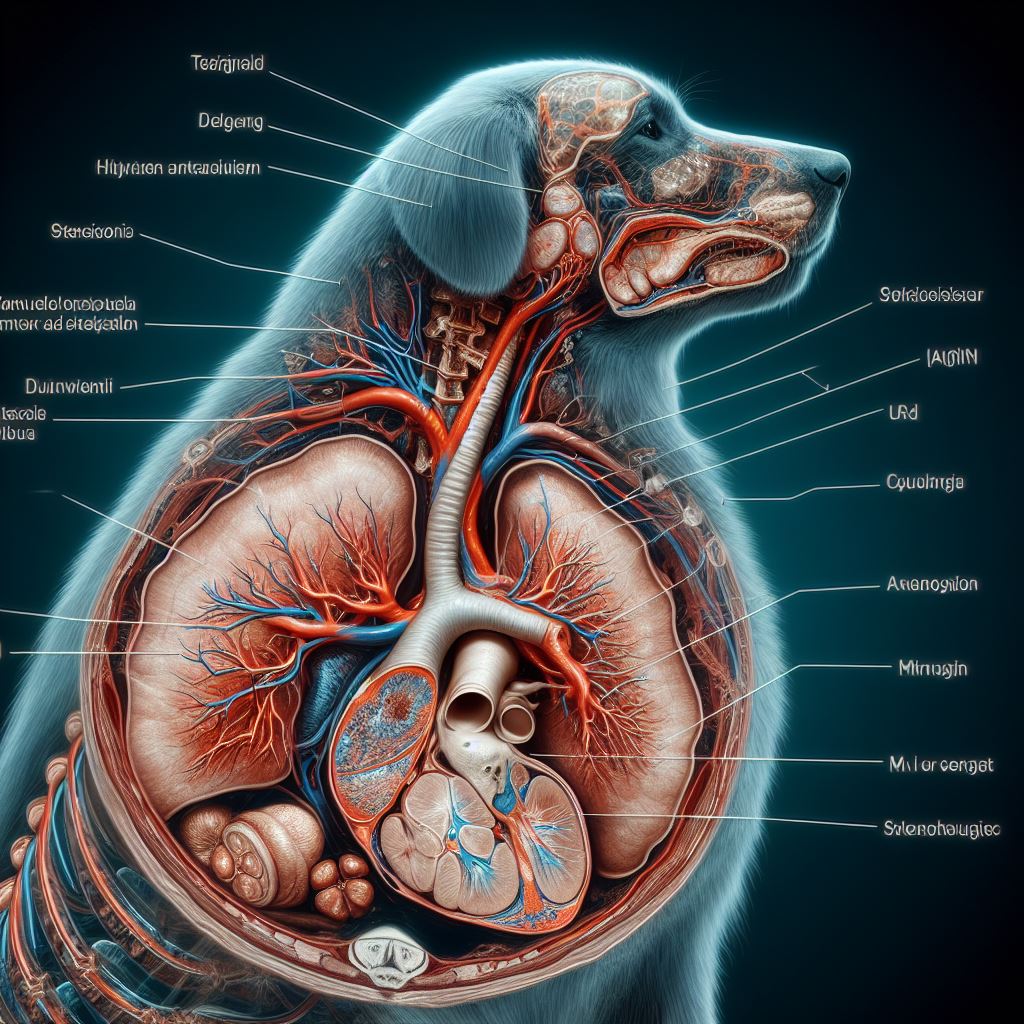

강아지 기관지 협착증 원인과 증상, 치료 방법 알아보기 사진

강아지 기관지 협착증 원인

유전적 요인

일부 강아지는 유전적인 특성으로 인해 증상에 노출될 수 있습니다. 특정 유전자 변이가 있는 강아지는 호흡에 문제가 생길 가능성이 높아지며, 증상의 발병 가능성이 더 높아집니다.

환경적 요인

환경적 요인은 강아지의 기관지에 부정적인 영향을 미칠 수 있습니다. 공기 오염물질이나 화학 물질에 노출되는 것은 강아지의 호흡 기관에 염증을 유발하여 증상을 초래할 수 있습니다. 특히 실내에서 흡연하는 경우, 담배 연기에 함유된 유해 물질이 강아지의 기관지에 직접 영향을 줄 수 있습니다.

알레르기 반응

알레르기는 강아지의 기관지를 자극하여 협착을 유발할 수 있습니다. 흡입 알레르기 물질인 집진 진드기, 꽃가루, 먼지 등이 강아지의 호흡 기관에 접촉하면 기관지 염증이 발생할 수 있으며, 이는 증상을 야기할 수 있습니다.

감염성 요인

강아지가 감염에 걸릴 경우, 기관지에 염증이 발생하여 협착증이 발생할 수 있습니다. 바이러스나 박테리아에 감염된 경우, 면역 반응으로 인해 기관지 염증이 생기고, 이는 증상을 초래할 수 있습니다.

기타 요인

강아지의 기관지 협착에는 기후적인 조건도 영향을 미칠 수 있습니다. 예를 들어, 냉기나 습도가 높은 환경에서는 강아지의 호흡 기관이 좁아지고 염증이 생길 가능성이 높아집니다. 또한, 스트레스, 신체적인 압력, 비만 등도 증상을 악화시킬 수 있는 요인이 될 수 있습니다.